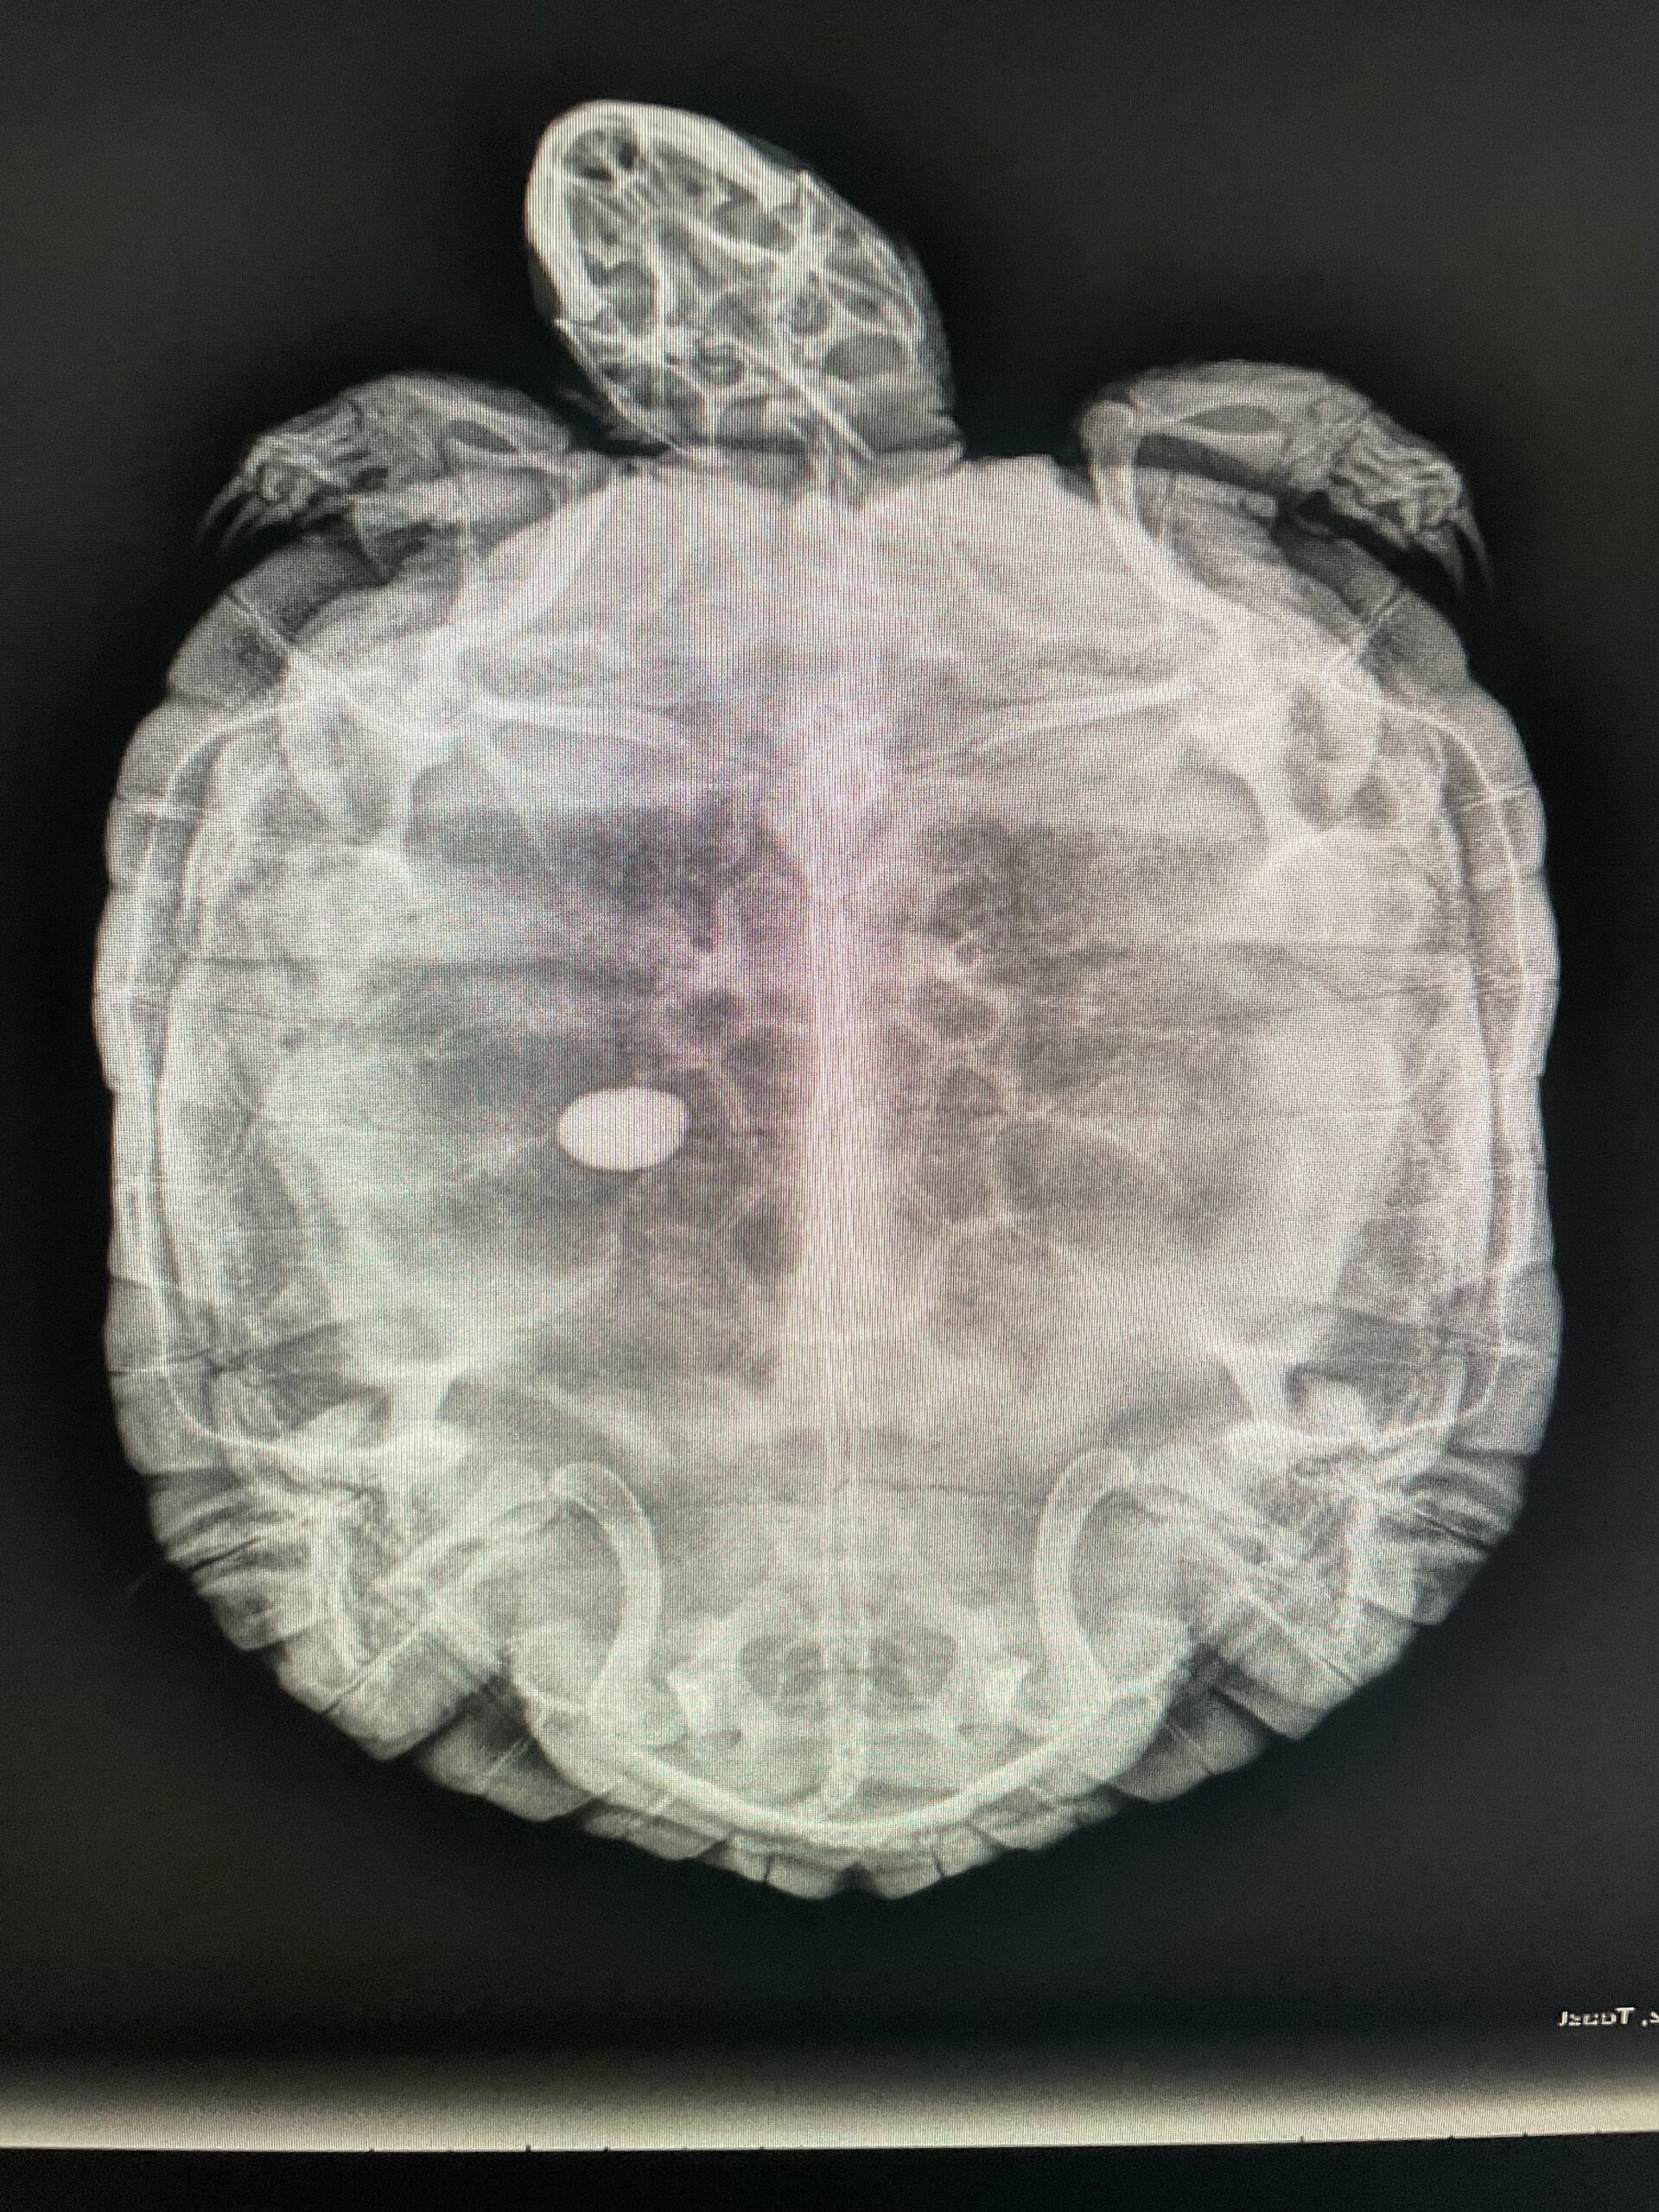

Some of the medical conditions we see in exotic pets include:

- Dental disease

- Parasites

- Metabolic bone disease

- Nutritional deficiencies

- Reproductive issues